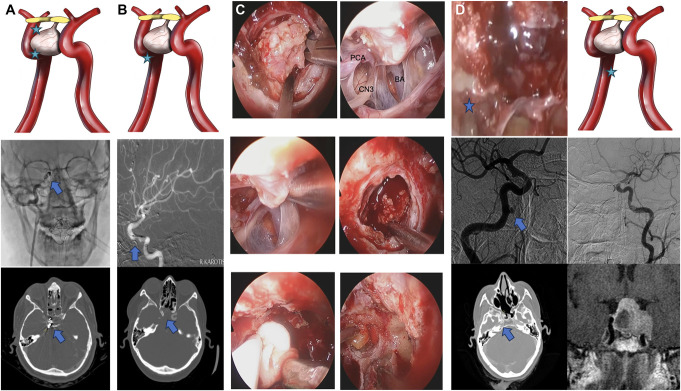

背景与目的:内窥镜鼻内手术(EES)因其全景性和详细的解剖定义而成为治疗鞍区和鞍旁病变的首选方法。本研究旨在回顾EES的主要动脉损伤,这是一种罕见但严重的并发症,具有高死亡率和发病率。方法:回顾性分析1997年8月至2024年2月在我中心/神经外科进行的5640例EES手术中的15例患者。该研究侧重于围手术期和术后管理策略,强调使用氧化再生纤维素(Surgicel®)/明胶凝血酶基质(Floseal®)和多学科合作来实现止血。结果:大动脉损伤发生率为0.2%,患者平均年龄38.4岁,男女比例为10:5。最常见的肿瘤是腺瘤(n = 7)和脊索瘤(n = 5)。6例患者中最常见的出血动脉分别是颈内动脉海绵状段和颈门旁动脉。10例患者出现低流量出血,5例患者出现高流量出血,其中4例复发(P < 0.05)。3例颈动脉段高流量出血患者行数字减影血管造影置入支架或线圈栓塞,1例高流量出血患者行数字减影血管造影监测脑血流。1例患者在随访第14个月时死于心肌梗死,1例患者出现左偏瘫。结论:该研究强调了术前计划、外科专业知识和多学科团队合作在EES中处理主要动脉损伤的重要性。作者主张发展标准化的治疗算法,以改善这些患者的预后。这些发现弥补了EES中处理颈内动脉损伤的有限文献,强调了持续研究和算法开发的必要性。

Results: The incidence of major arterial injury was 0.2%, with a mean patient age of 38.4 years and a female-to-male ratio of 10:5. The most common tumors were adenomas (n = 7) and chordomas (n = 5). The most commonly bleeding arteries in 6 patients each are the cavernous segment of the internal carotid artery and the paraclival carotid artery. Low-flow bleeding was observed in 10 of our patients, while high-flow bleeding was seen in 5 patients, 4 of whom were recurrent cases ( P < .05). In 3 patients with high-flow bleeding from segments of the carotid artery, digital subtraction angiography was performed for stent placement or coil embolization, while in 1 patient with high-flow bleeding, digital subtraction angiography was used for monitoring cerebral blood flow. One of our patients died of a myocardial infarction at the 14th month of follow-up and 1 of our patients developed left-hemiparesis.